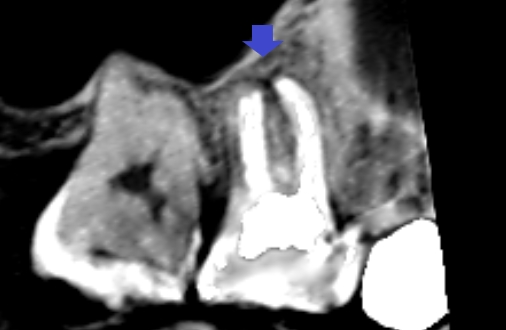

しかし、CTの画像を少しずらしてみると、同じ近心頬側根の中にもう一つの未治療の根管がみられました。青い矢印の先に黒い筋がみられます。これが未治療の根管です。